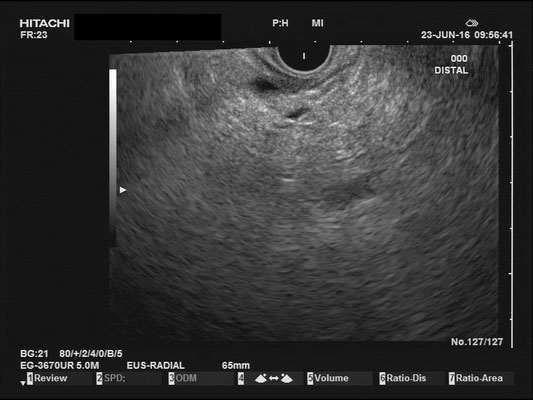

Normal findings - Pancreas / Common bile duct (CBD)

Pancreas

The images above depict a thorough inspection of the pancreas, as seen in an radial EUS Examination. We begin (hopefully ;) bei identifying the uncinate process between the golden V, which is formed by the aorta/V. cava and the mesenteric vessels. After spotting die usually hypoechoic ventral pancreatic root, the duodenal papilla can be identified (for a more detailed approach, please visit "Learning Endosono"). By following the splenic vein, the body and tail of the pancreas can be examined.